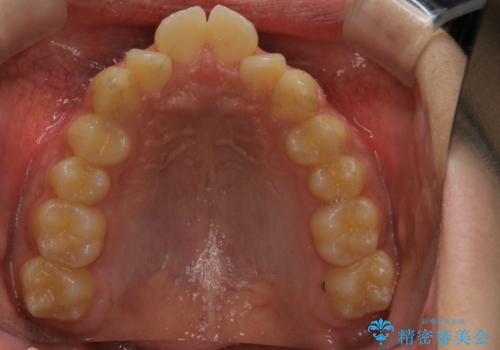

非抜歯で劇的に出っ歯を改善!インビザラインとカリエールの組み合わせ治療

- 患者様、出っ歯のお悩みで来院されました。

骨格の分析を行ったところ上顎も出てはいるのですが、下顎が引っ込んでいる状態であるということがわかりました。

よって上顎の歯を抜いて治療をするのではなく、カリエールという器具を使用して下顎を前に引っ張り出しながら上顎を引っ込めるという治療を行うことにしました。